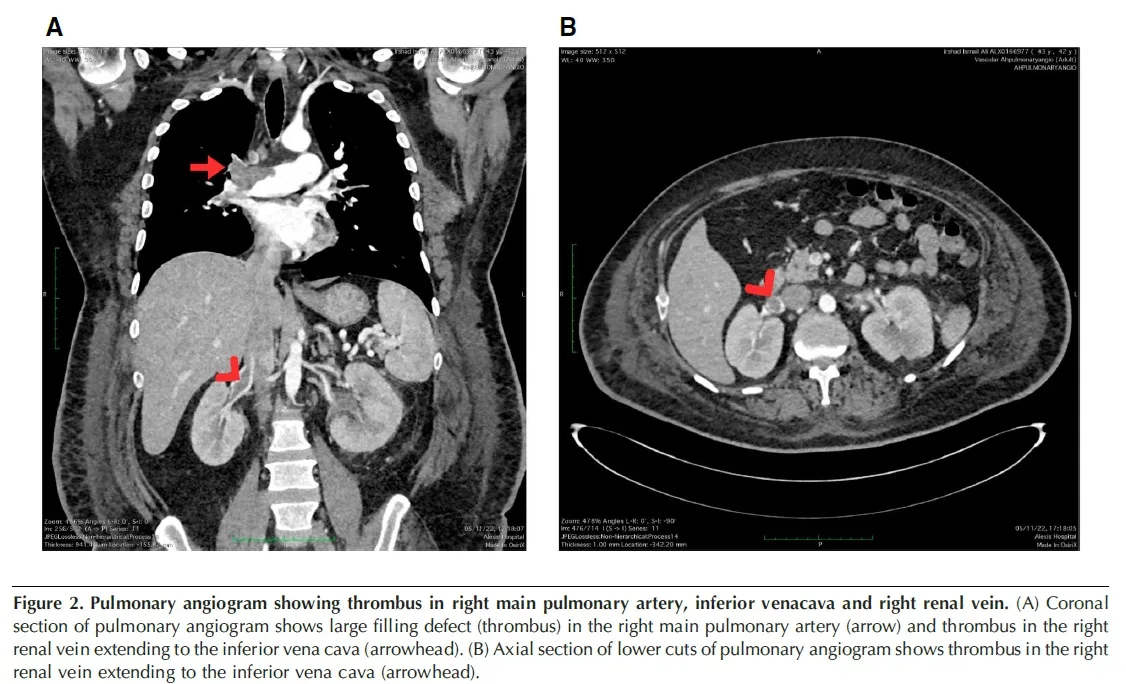

“Doutor, é só um remédio natural”: Uma possível armadilha para o rim!